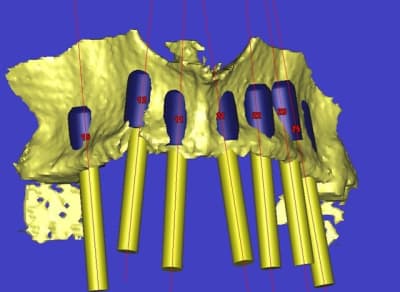

Précisions,ce projet n'a été possible que grâce à Posit pour l’étude 3D (indispensable, merci Alain) et la société BioBank, en particulier Raphaël Bardonnet dont la compétence et la disponibilité m'ont ouvert l’accès à un domaine peut connu, celui du traitement de l’os de donneur vivant.

L’idée de base est d’obtenir un greffon adapté à la zone à greffer, et de donner plus de chance à la nature de faire son travail de reconstruction.

Dans un premier temps, les greffons sont préparés manuellement par votre serviteur, mais ensuite la machine outil prendra le relais, dés que seront résolus les petits problèmes d’environnement.

Une fois les greffons préparés, ils sont traités par un procédé spécifique à Biobank (CO2 supercritique) puis stérilisation (rayons gamma), et vous le verrez la pose devrait être extrêmement simplifiée.

l'étude en partant des blocs standards

La première diapo est un essai pour justifier le concept (os non destiné à une utilisation greffe)

la deuxième est "tapée" dans une tête de femur de mauvais qualité (rejetée)

la troisième et suivante ce sont "les greffons" définitifs.